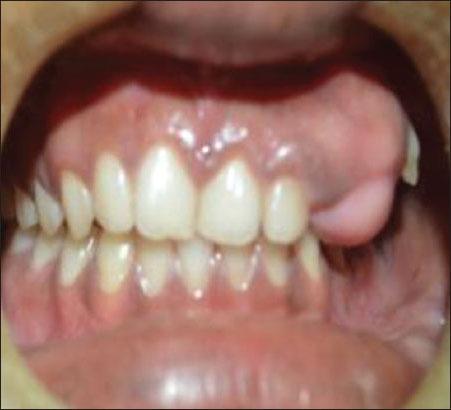

Ossifying fibroma is a rare benign osteogenic neoplasm arising from undifferentiated cells of the periodontal ligament. Ossifying fibroma have a well-defined border that differentiates it from fibrous dysplasia clinically, these tumors manifest as a round or ovoid, expansile, painless, slow-growing mass may displace the roots of adjacent teeth and also cause root resorption. They occur at second to fourth decade of life. Radiologically the lesion appears as a dense radiopaque mass surrounded by a thin, well-defined regular radiolucent rim. Patient underwent thorough history taking and complete face, ear, nose, and throat examination. Computed tomography maxilla, orthopantomogram, paranasal sinus reveals entire maxillary sinus involved in one case. Nasal septum deviated to the opposite side, airway reduced on the side of swelling seen in one case. Root resorption seen in two cases and missing teeth in seen in case 1. In our study in case 1, the tumor involved maxillary sinus, medial wall of the nose. The tumors were excised by Weber-Fergusson and in case 2 the tumor was excised by maxillary vestibular approach. Overall recurrence rates after resection is reported to range from 30 to 56%.